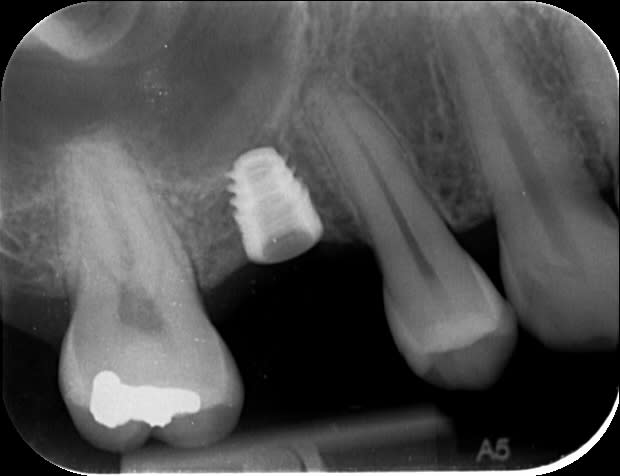

Interactive RP 4,3x6mm

Bite-Wing à 4 ans post-op

c'est donc du legacy3 que j'ai posé (mal, bien 10° dans le vague sur la 16) ce matin.

Ça fait vraiment tout rikiki mais j'ai pu constater une excellente stabilité primaire en brutalisant ce putain de transfert qui veux jamais quitter son implant.

j'ai tout laissé sous la gencive vu que j'ai du faire un petit ménage avant de planter, La cicat avait fait un truc dégeux en 16, j'ai tout gratté.